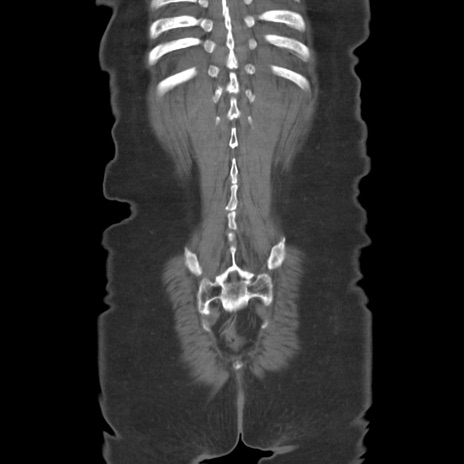

症例19(冠状断像)

【症例】80歳代女性

【主訴】下腹部痛

【現病歴】約8時間前より下腹部痛の出現あり、救急外来受診。

【既往歴】両側付属器切除

【身体所見】意識清明、下腹部正中に手術痕あり、その部位に一致して圧痛と反跳痛あり。腸蠕動音は亢進。

【データ】WBC 9300、CRP 0.15